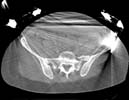

Subject: Pelvic & acetabular fracture

A 19 year old woman fell/jumped from the third floor.

Attached some of the X-rays and CT pictures. Apologizes for the quality of the imaging. What are your recommendations for treatment of the pelvic/acetabular and ankle injury?

Pelvic CT - Click to Magnify

Acetabular CT - Click to Magnify